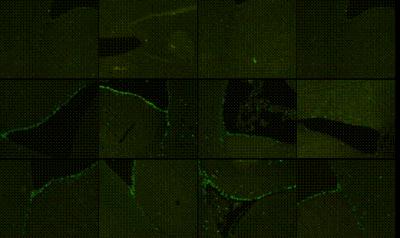

Neural stem cells proliferate in the subventricular zone and hippocampal dentate gyrus of adult mammals. However, the number of endogenous neural stem cells is insufficient to prevent cerebral ischemia/reperfusion injuries such as vascular dementia, so it is important to stimulate endogenous neural stem cell proliferation and differentiation. The ginkgo biloba extract EGb761 effectively and safely treats memory loss and cognitive impairments in patients with senile dementia. Prof. Yuliang Wang and team from Weifang Medical University observed the effects of EGb761 on proliferation of neural stem cells in the subventricular zone and dentate gyrus of rats with vascular dementia. Researchers found that the ginkgo biloba extract EGb761 promoted and prolonged the proliferation of neural stem cells in the subventricular zone and dentate gyrus of rats with vascular dementia. The cells continued to proliferate at 4 months. EGb761 also significantly improved learning and memory in rats with vascular dementia. These findings which were published in the Neural Regeneration Research (Vol. 8, No. 18, 2013) provide a new idea and approach to further explore the induced proliferation of neural stem cells in situ in the treatment of vascular dementia.

Article: " A ginkgo biloba extract promotes proliferation of endogenous neural stem cells in vascular dementia rats " by Jiwei Wang2, Wen Chen1, Yuliang Wang1 (1 Department of Physiology, Weifang Medical University, Weifang 261042, Shandong Province, China; 2 School of Medicine, Shandong University, Jinan 250012, Shandong Province, China).